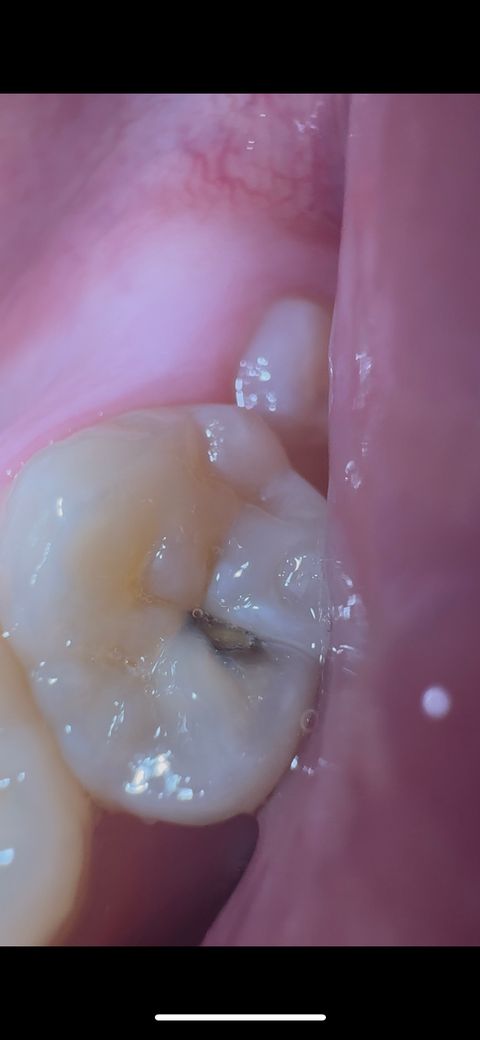

어금니에 충치 발생했습니다 당장 치료해야하나요

오른쪽 사랑니 나기 전 어금니 입니다

1년 전 쯤 이빨이 깨졌는데

아니겠지 라고 생각하고 넘겼는데

치아 시린 느낌이 더 이상 부정할 수 없게 만드네요

거의 종일 시리고

음식물 씹을 때 아프진 않은데

껌이나 젤리 같은 식감의 음식을 씹을 때 찌릿해서

차가운 것을 등에 갑자기 댄 것 처럼 깜짝 놀라요